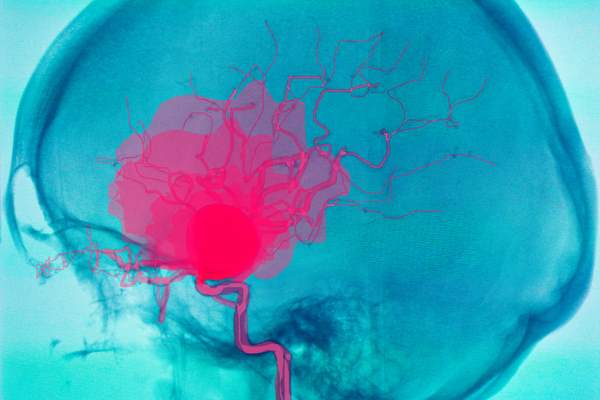

The aneurysm is one dilation of the artery, as a result of injury or weakening, usually attributable to genetic components: the affected space “swells”, taking the form of a balloon. On the aneurysm, the artery wall is thinner and weaker, which is why it continues to dilate as a result of blood stress. There break up it doesn’t happen in all individuals (bleeding impacts 0.5-3% of instances), but when it does the implications are very severe.

Aneurysms can have variable form and have an effect on a number of blood vessels (cerebral arteries, belly or thoracic aorta); cerebral aneurysm often develops the place an intracranial artery bifurcates. In line with the scale, we will distinguish them in:

When it’s small in dimension, a Unruptured mind aneurysm sometimes doesn’t give any signs. When it will get greater, nonetheless, it might trigger extreme headache and even disturbances in imaginative and prescient and speech, tingling within the limbs and weak point if it compresses nerves or mind tissue. There rupture and its hazard lastly they’re notably influenced by form of the aneurysm and its location: very giant and irregular aneurysms expertise bleeding extra steadily.

cerebral anuerism rupture

Semnic / shutterstock.com